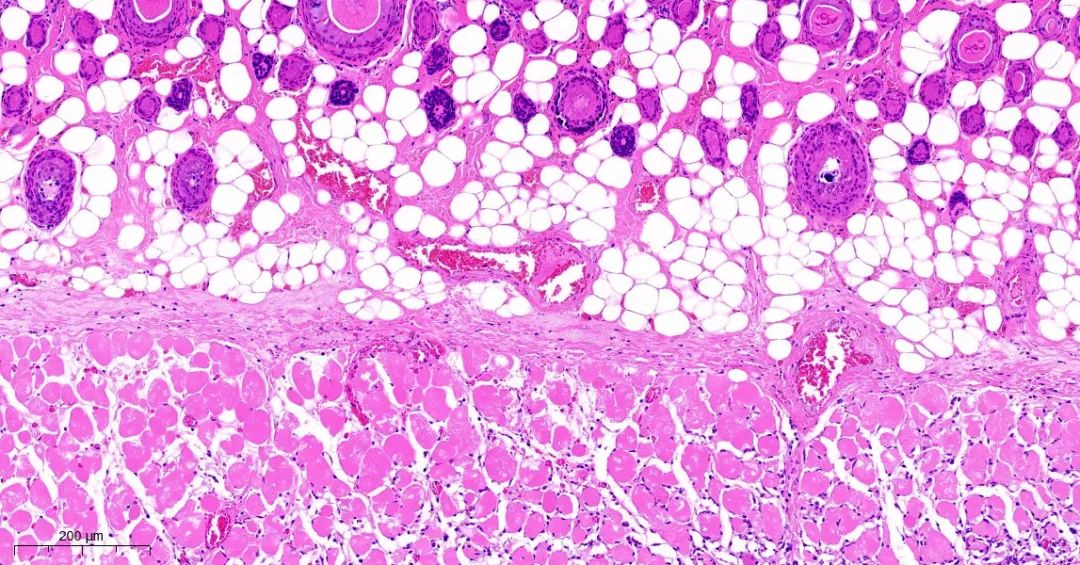

取正常对照组及模型组大鼠背部皮肤标本,常规固定,石蜡切片,HE染色,观察皮肤组织学变化。

模型1组皮组织切片对比